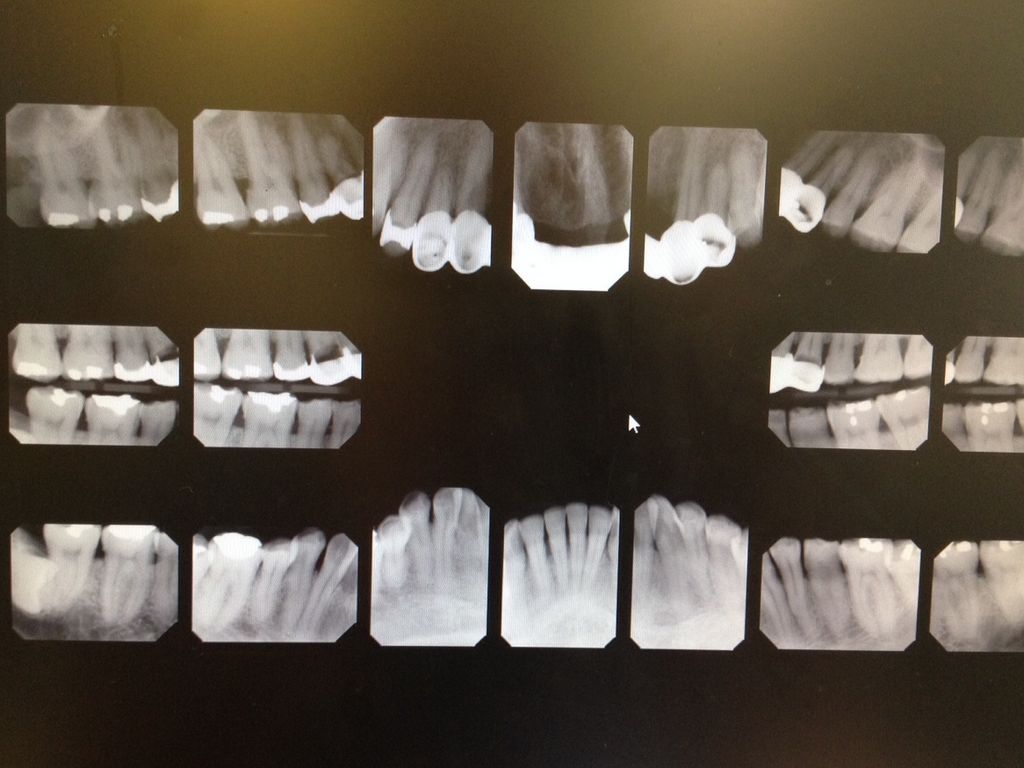

PATIENT HISTORY

41 year old male.

No known drug allergies or medications.

Chief Complaint: "I have fake teeth in front but I want them glued back."

FMX taken.